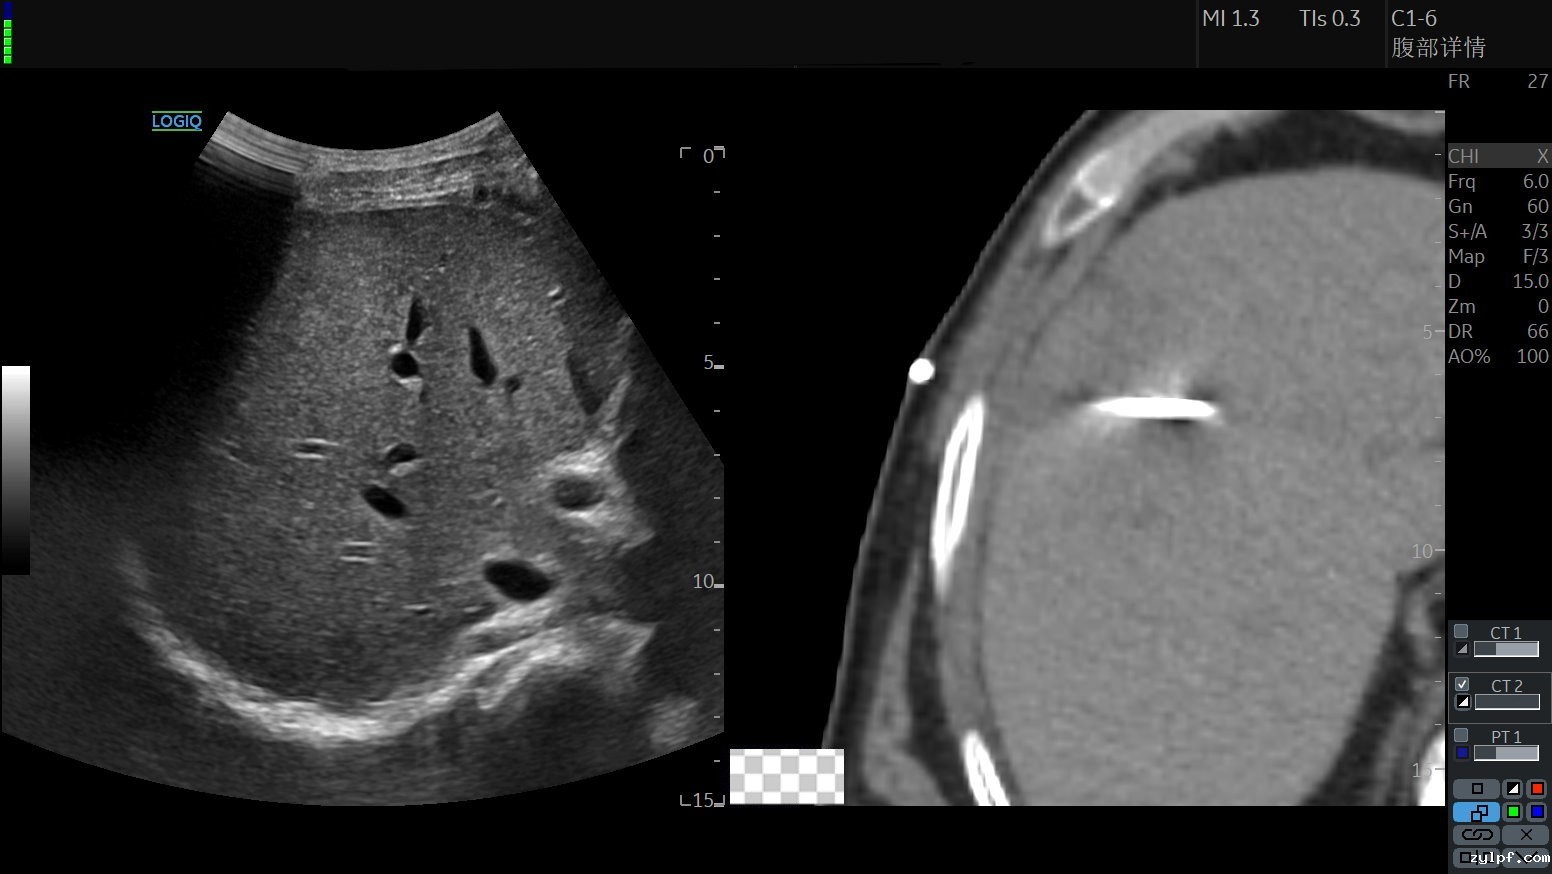

患者1食管癌术后,我院PET-CT提示肝脏高代谢区域,考虑恶性肿瘤,无法明确为新发病灶肿瘤或转移病灶,拟行活检,常规超声及普通CT病灶显示模糊,定位精准性明显不足。

左图为普通超声图像,右图为普通CT图像